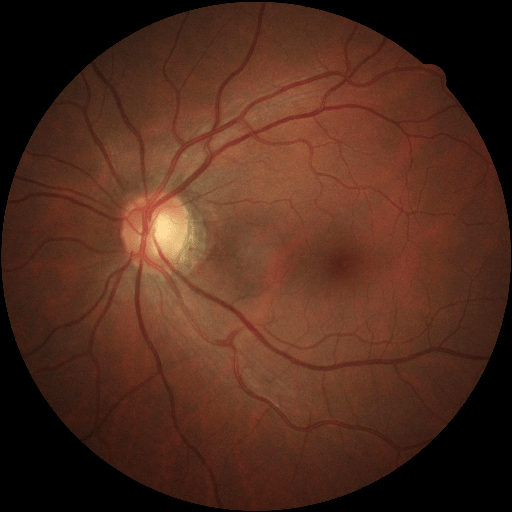

We conducted a case study on diagnosing diabetic retinopathy with ensembles of DL models. For benchmarking the performance of our ensemble-based solutions under the scheme described in Sec.3.3, we used two popular collections of diabetic retinopathy image data, the Kaggle Diabetic Retinopathy dataset [22] (hereafter referred to as “Kaggle-DR”) and the Messidor-2 dataset [23], each respectively consisting of and high resolution images. Diabetic retinopathy is graded into five SLs, as displayed in Figure 2. Following the problem setup used in previous papers [24], we trained models to distinguish the referable (SL2-4) cases from the non-referable ones (SL0 & SL1) (see Section B.1 for more detailed descriptions). We also tested our trained ensemble models on two o.o.d. image datasets (ImageNet [25] and CIFAR-10 [26]) to examine their capabilities of identifying o.o.d. inputs (see Section B in the supplementary materials).

The Kaggle-DR dataset comprises high resolution images. The presence of diabetic retinopathy is rated into five different SLs: no-DR (SL0), mild (SL1), moderate (SL2), severe (SL3), and proliferate (SL4), as illustrated in Figure 2. We divided the Kaggle-DR dataset into a development set and a test set, which respectively consisted of and images. The data in the development set were used to train and validate our Deep Learning (DL) models. The Messidor-2 dataset [38] that consisted of images was also used in our experiment as an additional dataset to test the true generalization performance of the models trained on the Kaggle-DR dataset. Images in Messidor-2 dataset were graded into the five SLs as in the Kaggle-DR dataset. Figure S.1 provides an illustration of the datasets used in our experiments.